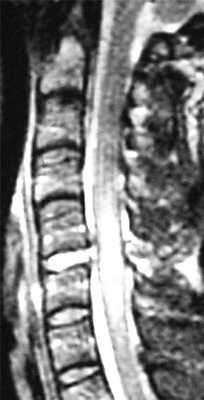

Особую категорию составляют пациенты, у которых, несмотря на наличие неврологической симптоматики, не выявляется изменений при рентгенографии или КТ. Число таких пациентов составляет около 10%. Среди различных механизмов подобных травм наиболее вероятна кратковременная компрессия спинного мозга задней продольной связкой и дисками, либо, жёлтой связкой и пластиной дуги. Посколько резкие сгибания и разгибания наблюдаются при высокой подвижности в сегментах, такие травмы более вероятны в шейном отделе позвоночника. Спондилолиз усугубляет эту ситуацию, приводя к центральному синдрому спинного мозга. В этих случаях необходимой является МРТ позвоночника. Характерными находками, которые мы часто видим при травмах при МРТ в СПб, являются отёк спинного мозга и гематома, причём последняя при МРТ позвоночника плохим прогностическим фактором в отношении восстановления неврологического дефицита. К наиболее тяжелым осложнениям шейной травмы относится расслоение магистральных артерий, определяемое по МРТ, МРА или КТ и КТА. В высоком поле такой вид травм лучше виден чем в открытом МРТ. МРТ СПб позволяет выбирать место МРТ, однако, острая травма шейного отдела позвоночника требует высокоспециализированного нейрохирургического отделения

МРТ шейного отдела позвоночника. Т2-взвешенная сагитальная МРТ. Острая травма с повреждением задних элементов позвонков и отеком спинного мозга.

МРТ шейного отдела позвоночника. Острая травма. Отёк спинного мозга. Сагиттальная Т2-взвешенная МРТ.